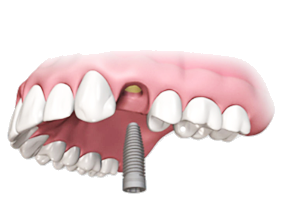

Восстановление зуба на имплантате

Имплантация

Имплантология - это восстановление утраченных зубов методом вживления в челюсть титановых аналогов корней зубов.